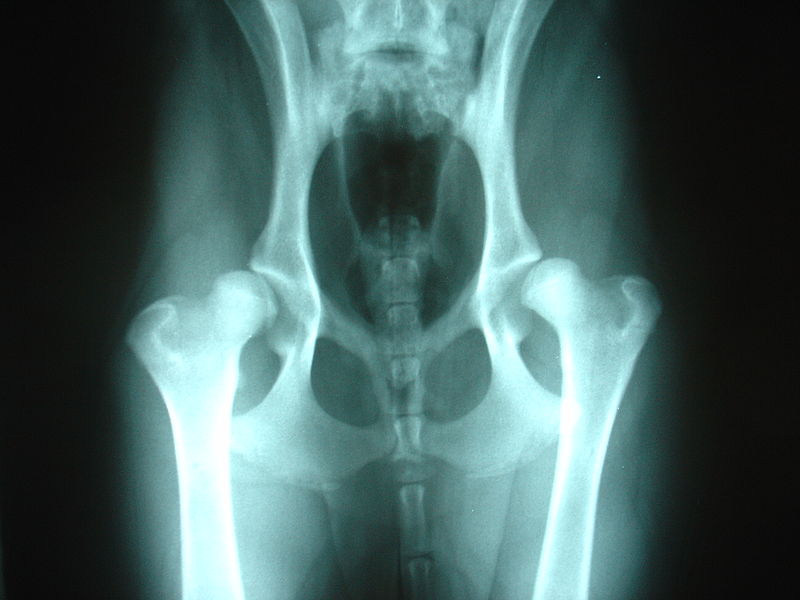

Není všeobecně známo, že výsledek "B" může být trochu "různorodý" a nejednou se stalo, že nejeden odborný posuzovatel naměřil "A" Béčku a naopak "B" Áčku. Přičemž velmi záleží na provedení RTG snímku prováděného moderním typem rentgenologické digitalizace, pro maximální kvalitu zhotovených rentgenogramů, nikoliv běžný rentgen u obecného veterináře, plus následně velmi závisí na úhlu měření. To pro základ vysvětlení jistě stačí. :) Jak je tedy možné, že mnozí z nově příchozích a bohužel i z těch, kteří existují s dalmatiny už nějakou dobu, se pohoršují nad "B" přičemž se nejedná o špatný zdrav. stav psa. Což u kyčelního kloubu typu "C" , "D" , "E" či loketního kloubu typu "2" , "3" říci nemohu.

Pro DYSPLAZII V PRAXI to znamená, že posudky jednotlivých veterinářů a rtg můžou být:

- různě přísné nebo naopak mírné vyhodnocení rtg..

- různé výsledky i v různém věku..

- jeden ten samý pes muže mít ve dvou zemích posouzení naprosto odlišné..